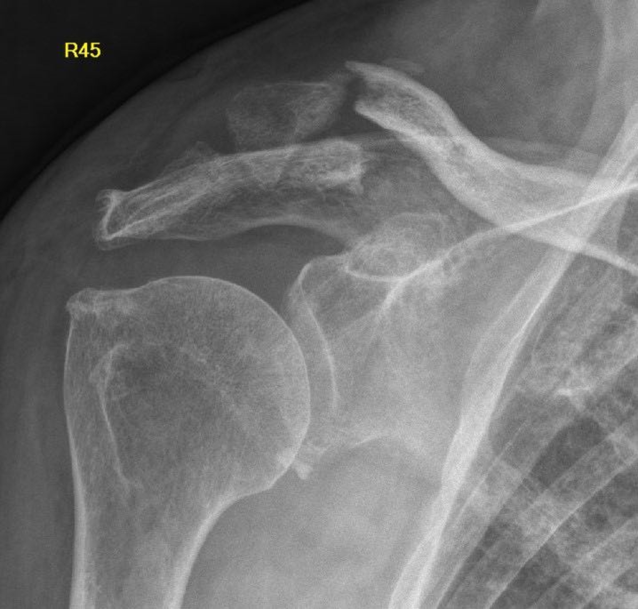

Bei einer Röntgenkontrolle zur Planung der Materialentfernung bei sonst asymptomatischer Patientin zeigte sich eine Verlagerung des verbliebenen K‑Drahtes nach intrathorakal/mediastinal (Abb. 2). Eine auswärts durchgeführte native Computertomographie (CT) bestätigte die Dislokation des K‑Drahtes und zeigte eine Perforation beider Pleurahöhlen und die Migration in das Mediastinum. Der K‑Draht verlief dorsal der A. vertebralis, zwischen Trachea und Ösophagus ohne eine Läsion dieser Strukturen (Abb. 3).

Abb. 2

Thoraxröntgenaufnahme, a.-p., stehende Patientin. Röntgenologische Darstellung mit der K‑Draht-Migration nach intrathorakal (rechts nach links)